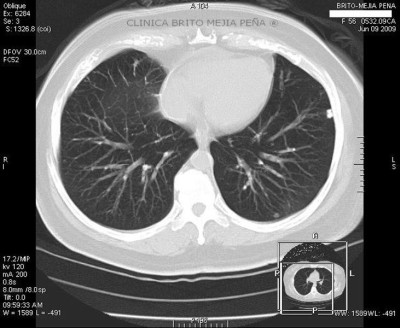

Pulmones vista aire

Post Image